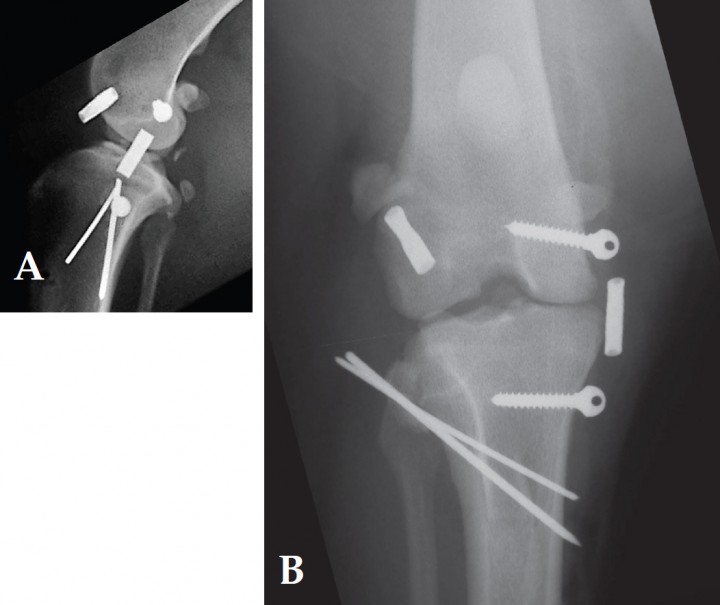

Al cabo de unos pocos días el perro comenzó a usar la extremidad. En la revisión, pasados 6 meses, se aprecia que el animal camina con normalidad y las radiografías muestran una buena resolución de la fractura (Fig. 5).

<p>Radiografías realizadas 6 meses después de la cirugía. A. Proyección lateral. B. Proyección postero-anterior.</p>

Figura 5

Radiografías realizadas 6 meses después de la cirugía. A. Proyección lateral. B. Proyección postero-anterior.